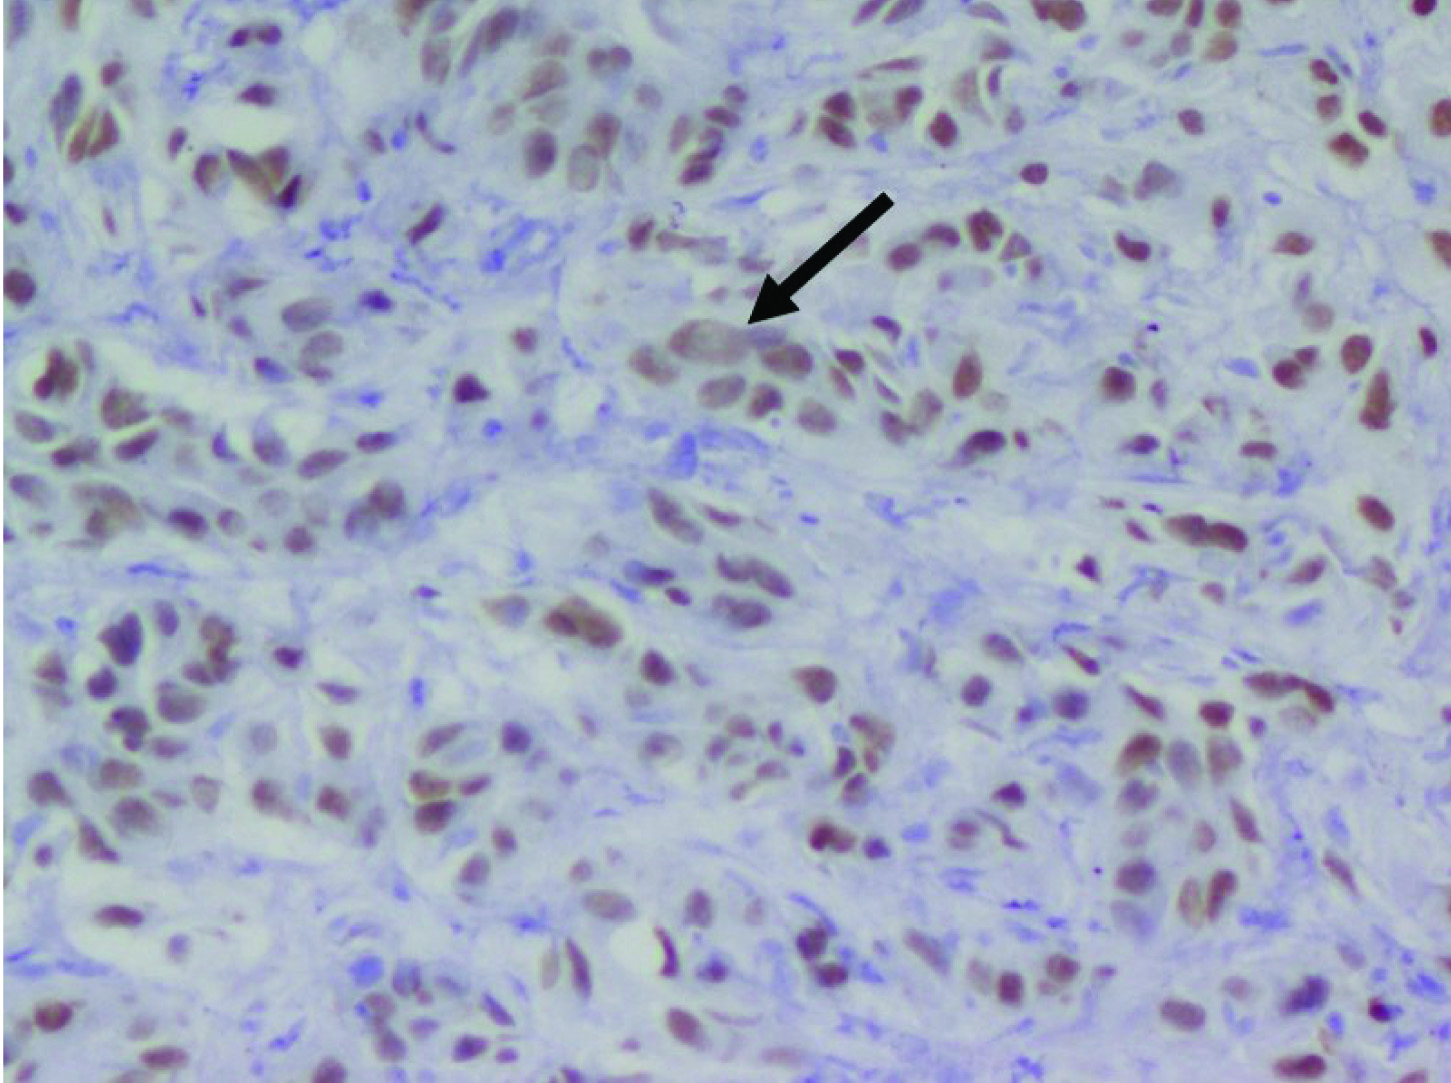

Contrast Enhanced Computed Tomography (CECT) of the abdomen showed a heterogeneously hypo-enhancing soft tissue lesion at the pelvis of right kidney [Table/Fig-1] with malignant para-aortic lymph nodes and a possible left adrenal gland metastasis. Computed Tomography (CT) guided biopsy from the lesion revealed an infiltrating tumor composed of spindle shaped cells with large hyperchromatic pleomorphic nuclei and moderate amount of eosinophilic cytoplasm (high N/C ratio) surrounded by desmoplastic stroma [Table/Fig-2]. Immunohistochemistry (IHC) showed the tumor cells stained positively for Paired box gene 8 (PAX8) and negative for Renal Cell Carcinoma (RCC), Cytokeratins 7 (CK7), Cytokeratin 20 (CK20) and Protein 63 (p63). Hemoglobin electrophoresis showed a normal adult pattern. Diagnosis of Collecting Duct Carcinoma (CDC) was established based on clinical setting, histology and IHC. A percutaneous left renal biopsy was done which was reported as Membranous Nephropathy (MGN) with immunofluorescence positive for IgG1 and negative for IgG4 staining. With the clinical background of an elderly male presenting with Nephrotic Syndrome (NS), a negative immune workup including APLA2R antibodies and renal biopsy suggestive of MGN with absent immunofluorescence staining for IgG4, a diagnosis of disseminated malignancy with secondary MGN was concluded. The nature of the disease and therapeutic options were discussed. Patient and his relatives wished for conservative approach without any definitive surgical or anticancer therapy. Patient was initiated on angiotensin converting enzyme inhibitors with statins and at last follow up, patient continued to have features of NS.

Tumor cells showing intense nuclearpositivity for PAX8 (thick arrow) with desmoplastic stroma (Magnification 40X; PAX8).